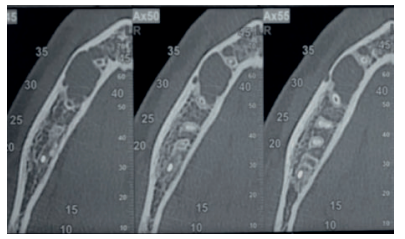

Se solicitó como prueba complementaria un CBCT mandibular. En los cortes panorámico, axiales y ortorradiales, se corroboró la presencia de lesión radiotransparente delimitada de contorno algo irregular y que no provocaba expansión de corticales (Figuras 1-4).